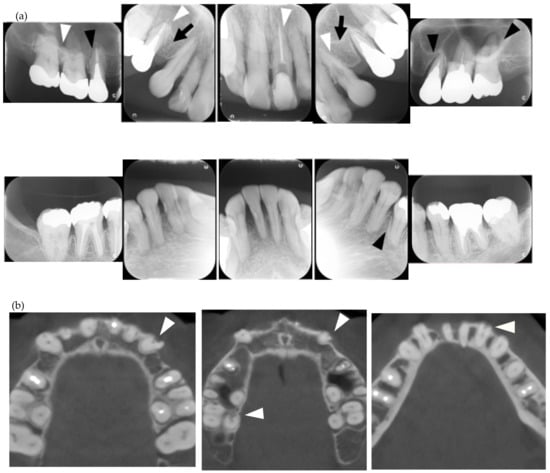

Figure 3.

Multiple external root resorption and calcinosis at the oral region in pt. 4. A dental X-ray photo and CBCT image of teeth and the deposition of calcinosis at the palatal site (a–c). The white arrowhead represents root resorption, the black arrowhead, PDL space widening, and the white arrow, calcinosis, while the black arrow shows a failure to close the space with orthodontic treatment.

In the present study, MERR was detected in four SSc patients, including one described in a case report (pt. 1) [12]. The causes of external resorption, including trauma, periodontal and periapical inflammation, orthodontic treatment, internal bleaching or tumors, were not found in the teeth having external resorption. Dental X-rays and CBCT images showed that MERR was observed in six, six, and four teeth in pts. 2, 3, and 4, respectively (Figure 1a, Figure 2a and Figure 3a). A widening PDL space was detected in all patients. A space between canines and premolars in the upper jaw was found in pts. 3 and 4 (Figure 2a and Figure 3a). Furthermore, the deposition of calcinosis in the nasal spur was noted in pts. 1, [12], 2, and 3, while calcinosis in the palatal plate was observed in pt. 4 (Figure 2c and Figure 3c).